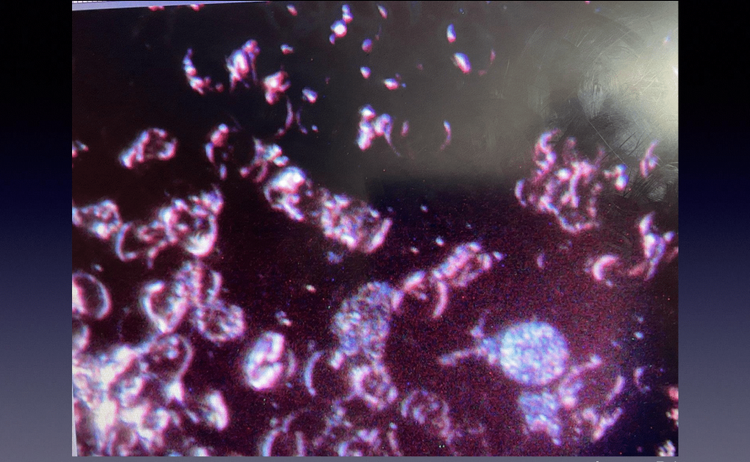

Pre-Metadichol

Here, the red blood cells are abnormally stacked together in long chains.

This stacking drastically reduces the useful red blood cell surface area and independent movement, severely restricting the red blood cells’ ability to carry oxygen/information throughout the body.

In addition, the tight stacking makes it almost impossible to observe any activity/inclusions within the red blood cells.

The dark area filled with bluish, long crystalline/thread-like objects indicates oxidative stress.

Every part of the first blood sample had a clearly visible background filled with these static objects.